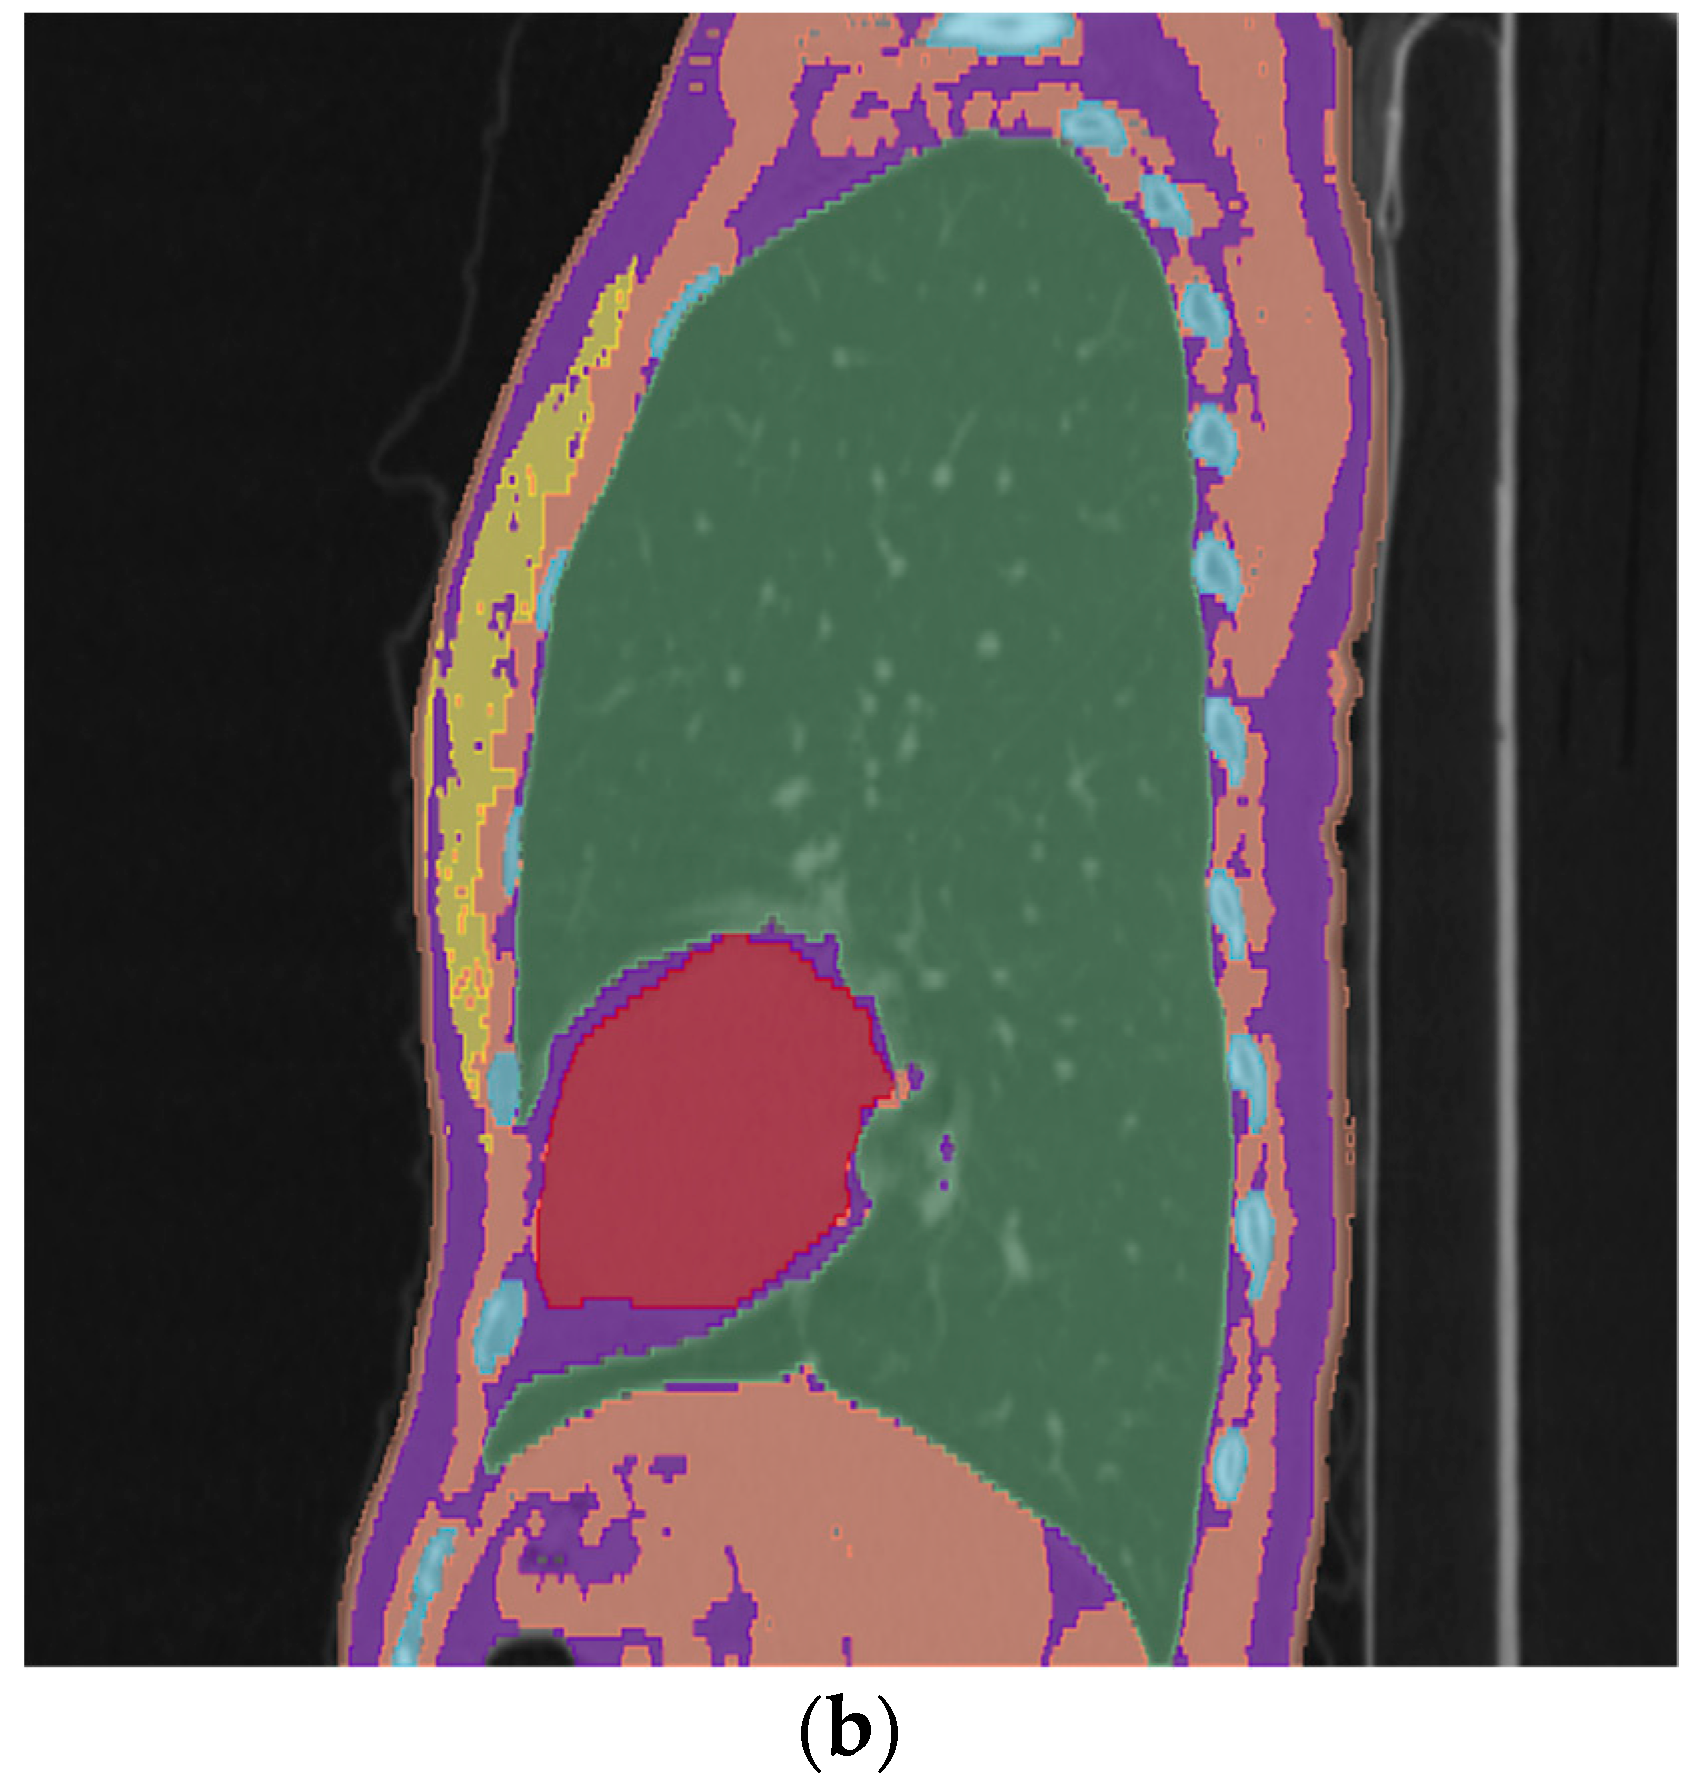

3.1. Voxelized Chest Models of Patients